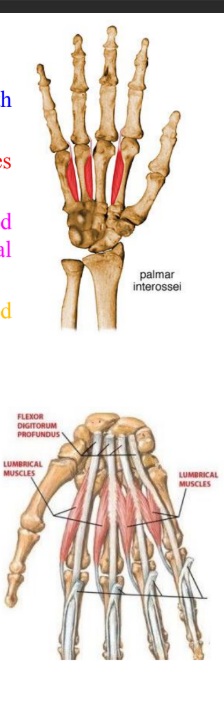

Interossei, palmar and lumbricals

ORIGIN | INSERTION | ACTION | INNERVATION | |

Palmar interossei | Palmar surfaces of 2nd, 4th and 5th metacarpals | Extensor expansions of digit and bases of proximal phalanges | Adduct digits towards axial line Assist lumbricals in flexing metacarpophalangeal joints and extending interphalangeal joints | Deep branch of ulnar nerve |

Lumbrical muscles | From tendon of flexor digitorum profundus | Dorsal digital expansion | Flex the metacarpophalangeal joints and extend the interphalangeal joints | 1st and 2nd lumbricals by median nerve 3rd and 4th lumbricals by deep branch of ulnar nerve |